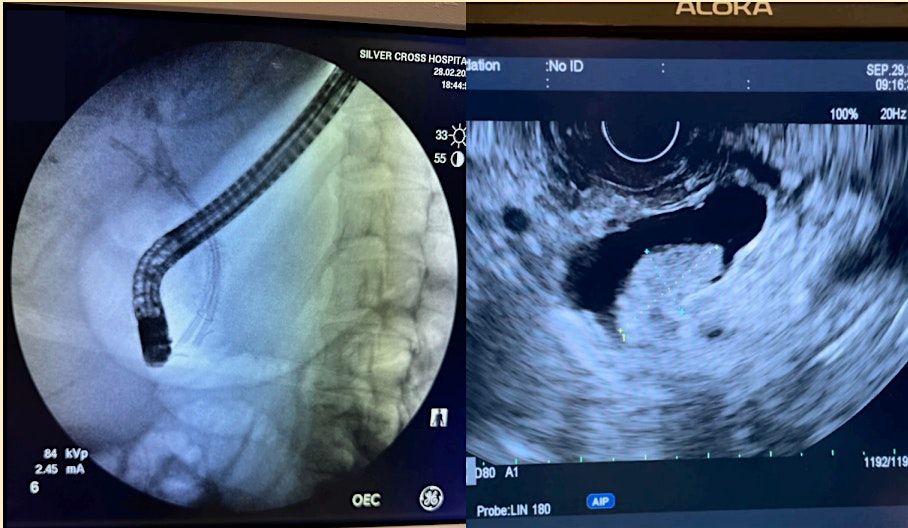

Gastroenterology and Endoscopy for Doctors, Nurses, and Associates

Welcome to the Gastroenterology and Endoscopy event for Doctors, Nurses, and Associates! Join us for a day of learning and networking at The Doubletree Hotel Chicago-Oak Brook, located at 1909 Spring Road, Oak Brook, IL. This in-person event will feature expert speakers, hands-on workshops, and the latest advancements in the field. Don't miss this opportunity to enhance your knowledge and connect with colleagues in the industry. Register now to secure your spot!